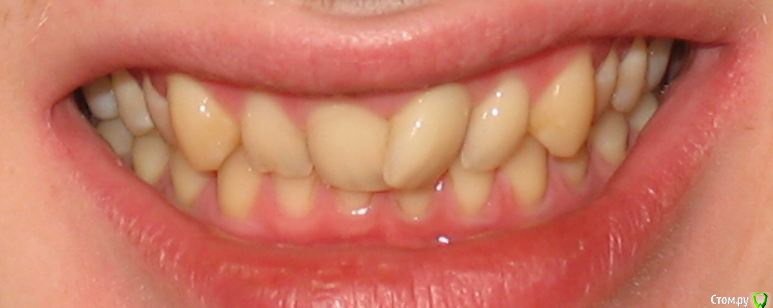

Мне 28 лет. У меня нет ни одной пломбы. Всю жизнь я хожу к стоматологом только на гигиеническую чистку. Последние несколько лет мне уже несколько врачей рекомендовали удалить четвёрки и поставить брекеты для исправления дистального прикуса. Один из ортодонтов также предлагал ЧЛХ нижней челюсти. Основной аргумент у врачей, что если не снизить нагрузку на дёсны от неправильного прикуса, то уже лет через 5 зубы начнут выпадать. Как видно на фото, дёсны уже значительно сползли, появился клиновидный дефект. С эстетической точки зрения меня всё устраивает. Хочу услышать ещё несколько мнений, как бороться с опусканием дёсен и стоит-ли заниматься исправлением прикуса.